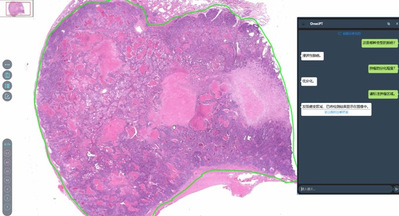

Artificial intelligence (AI)-enabled medical diagnostic tools are improving cancer screening accuracy, helping do...